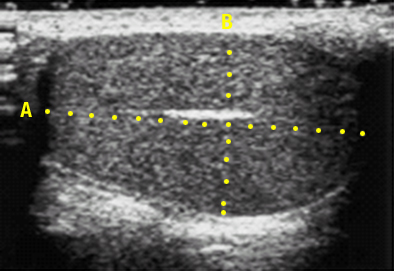

서 있는 자세에서 왼쪽 음낭 내 구불구불한 정맥류가 보이거나 만져진다면 쉽게 진단할 수 있다. 진단이 어려울 경우 복압을 높여 음낭을 살펴보는 발사바법(Valsalva)을 시행하면 진단에 도움이 된다. 1) 고환 크기 측정: 정계정맥류는 고환조직의 변성을 유발하게 되어 결과적으로 고환 용적을 감소시킨다. 특히 청소년기에는 양측 고환 용적에 차이가 있거나 고환이 성장하지 않는 경우 정계정맥류 교정술의 적응증이 되기 때문에 고환 용적을 측정하는 것이 중요하다. 고환 용적 측정기(orchidometer, ellipsoid ring)를 이용하면 고환 크기를 비교적 정확하게 측정할 수 있다. 2) 초음파 검사: 초음파 검사는 고환의 크기뿐만 아니라 늘어난 정맥의 크기와 개수를 알 수 있어 많이 사용되고 있다. 그러나 진단에 필수적인 검사는 아니다. 3) 정액 검사: 정계정맥류는 남성불임의 가장 흔한 원인이기 때문에 정계정맥류가 고환에 영향을 끼치고 있는지 알아보기 위해 정액 검사를 시행한다. 정계정맥류 환자가 불임이 아닌 다른 증상으로 병원에 오게 되더라도 정액 검사를 해 보면 대부분 이상 소견이 발견되므로 특별히 금지되는 이유가 없다면 정액 검사를 시행하는 것이 바람직하다. 4) 생식소 자극 호르몬 분비 호르몬(gonadotropin releasing hormone, GnRH) 자극 검사: 사춘기 이전의 소아에서 고환 기능 평가를 위한 방법이다. 생식소 자극 호르몬 분비 호르몬(GnRH)을 주사하고 황체형성호르몬(LH)와 여포자극호르몬(FSH) 수치를 3~4회 측정하여 주사 전 수치와 비교하여 판정한다. 5) 정맥조영술: 가장 정확한 방법이지만 침습적(피부를 통해 조직을 찌르는) 검사법이고, 고도의 검사 기교가 요구되므로 특별한 경우에만 시행한다. 6) 고환 조직 검사: 고환 조직 검사는 개방 생검이나 경피적 천자생검을 통하여 고환의 조직 일부를 얻는 검사이다. 고환의 상태를 가장 정확히 파악할 수 있는 방법이지만 침습적 이어서 제한된 경우에만 시행된다.

초음파에 의한 고환 용적 측정